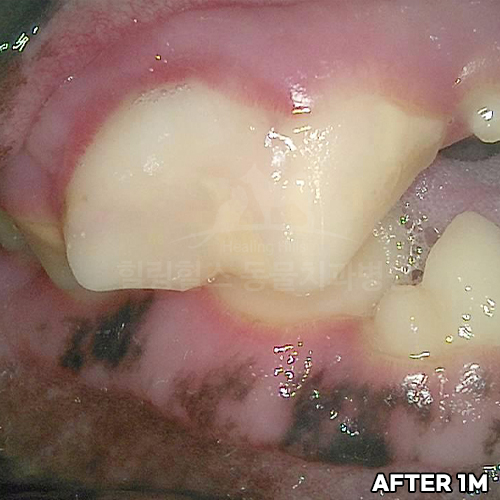

웰시코기의 아주 심한 파절치아를 강아지치과에서 수술하고 1년 뒤에도 잘 씹어요~!! - 동물치과 힐링힐스 -